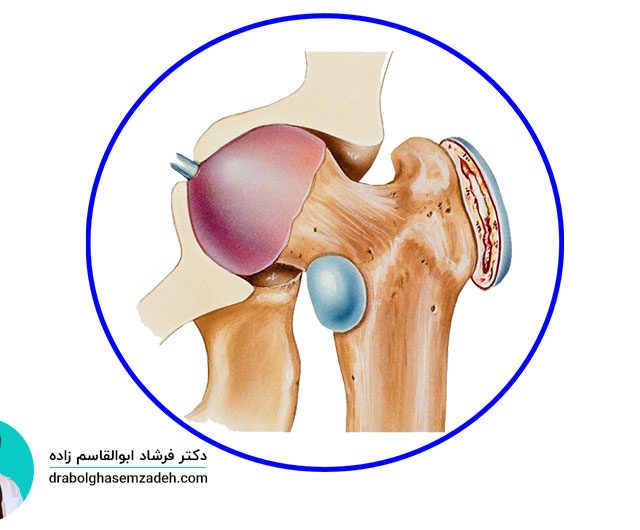

علت درد بازو

بیشتر افراد به هنگام داشتن بازو درد، علت آن را وارد شدن ضربه به آن می دانند. وارد شدن ضربه به بازو، یکی از دلایل درد بازو عنوان شده است؛ اما دلایل دیگری برای احساس درد در بازوها وجود دارند. برای درمان، درد بازو، مهم ترین کار تشخیص علت درد بازو است. علت درد، انتخاب […]...